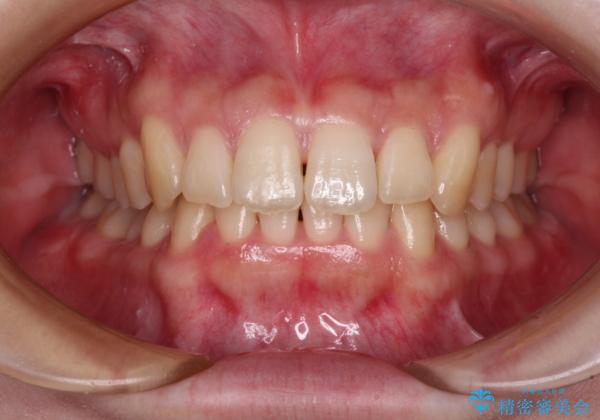

- 全体的な歯列の叢生を気にして来院された患者様です。

奥歯の咬み合わせを見ると、片方は上顎が下顎に対して相対的に前方にあり、他方は交叉した咬合の状態でした。

咬み合わせを改善するためには、上顎臼歯を後方に移動させた咬み合わせにする必要があります。

インビザライン単体で改善することも可能ですが、ディープバイトのためインビザライン単体で達成する可能性が低いと考えられたため、カリエール・ディスタライザーという補助装置を併用して、より確実性を上げることとしました。